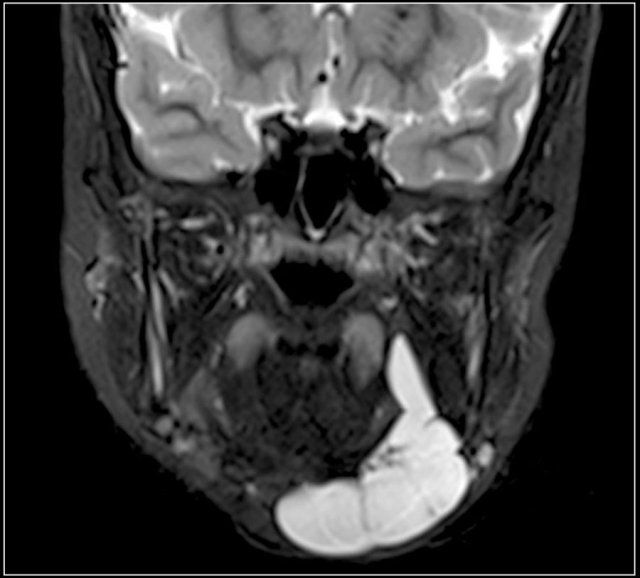

Here images of a six-month old boy with a vocal cord paralysis.

The MRI examination shows a mass between the parotid and submandibular gland (yellow arrow).

The signal characteristics are equal to the thymus (green arrow).

Ultrasound confirmed an ectopic thymic remnant (yellow arrow), with identical sonographic characteristics as the orthotopic thymus (green arrow).

Left: orthotopic thymus; right: ectopic thymus